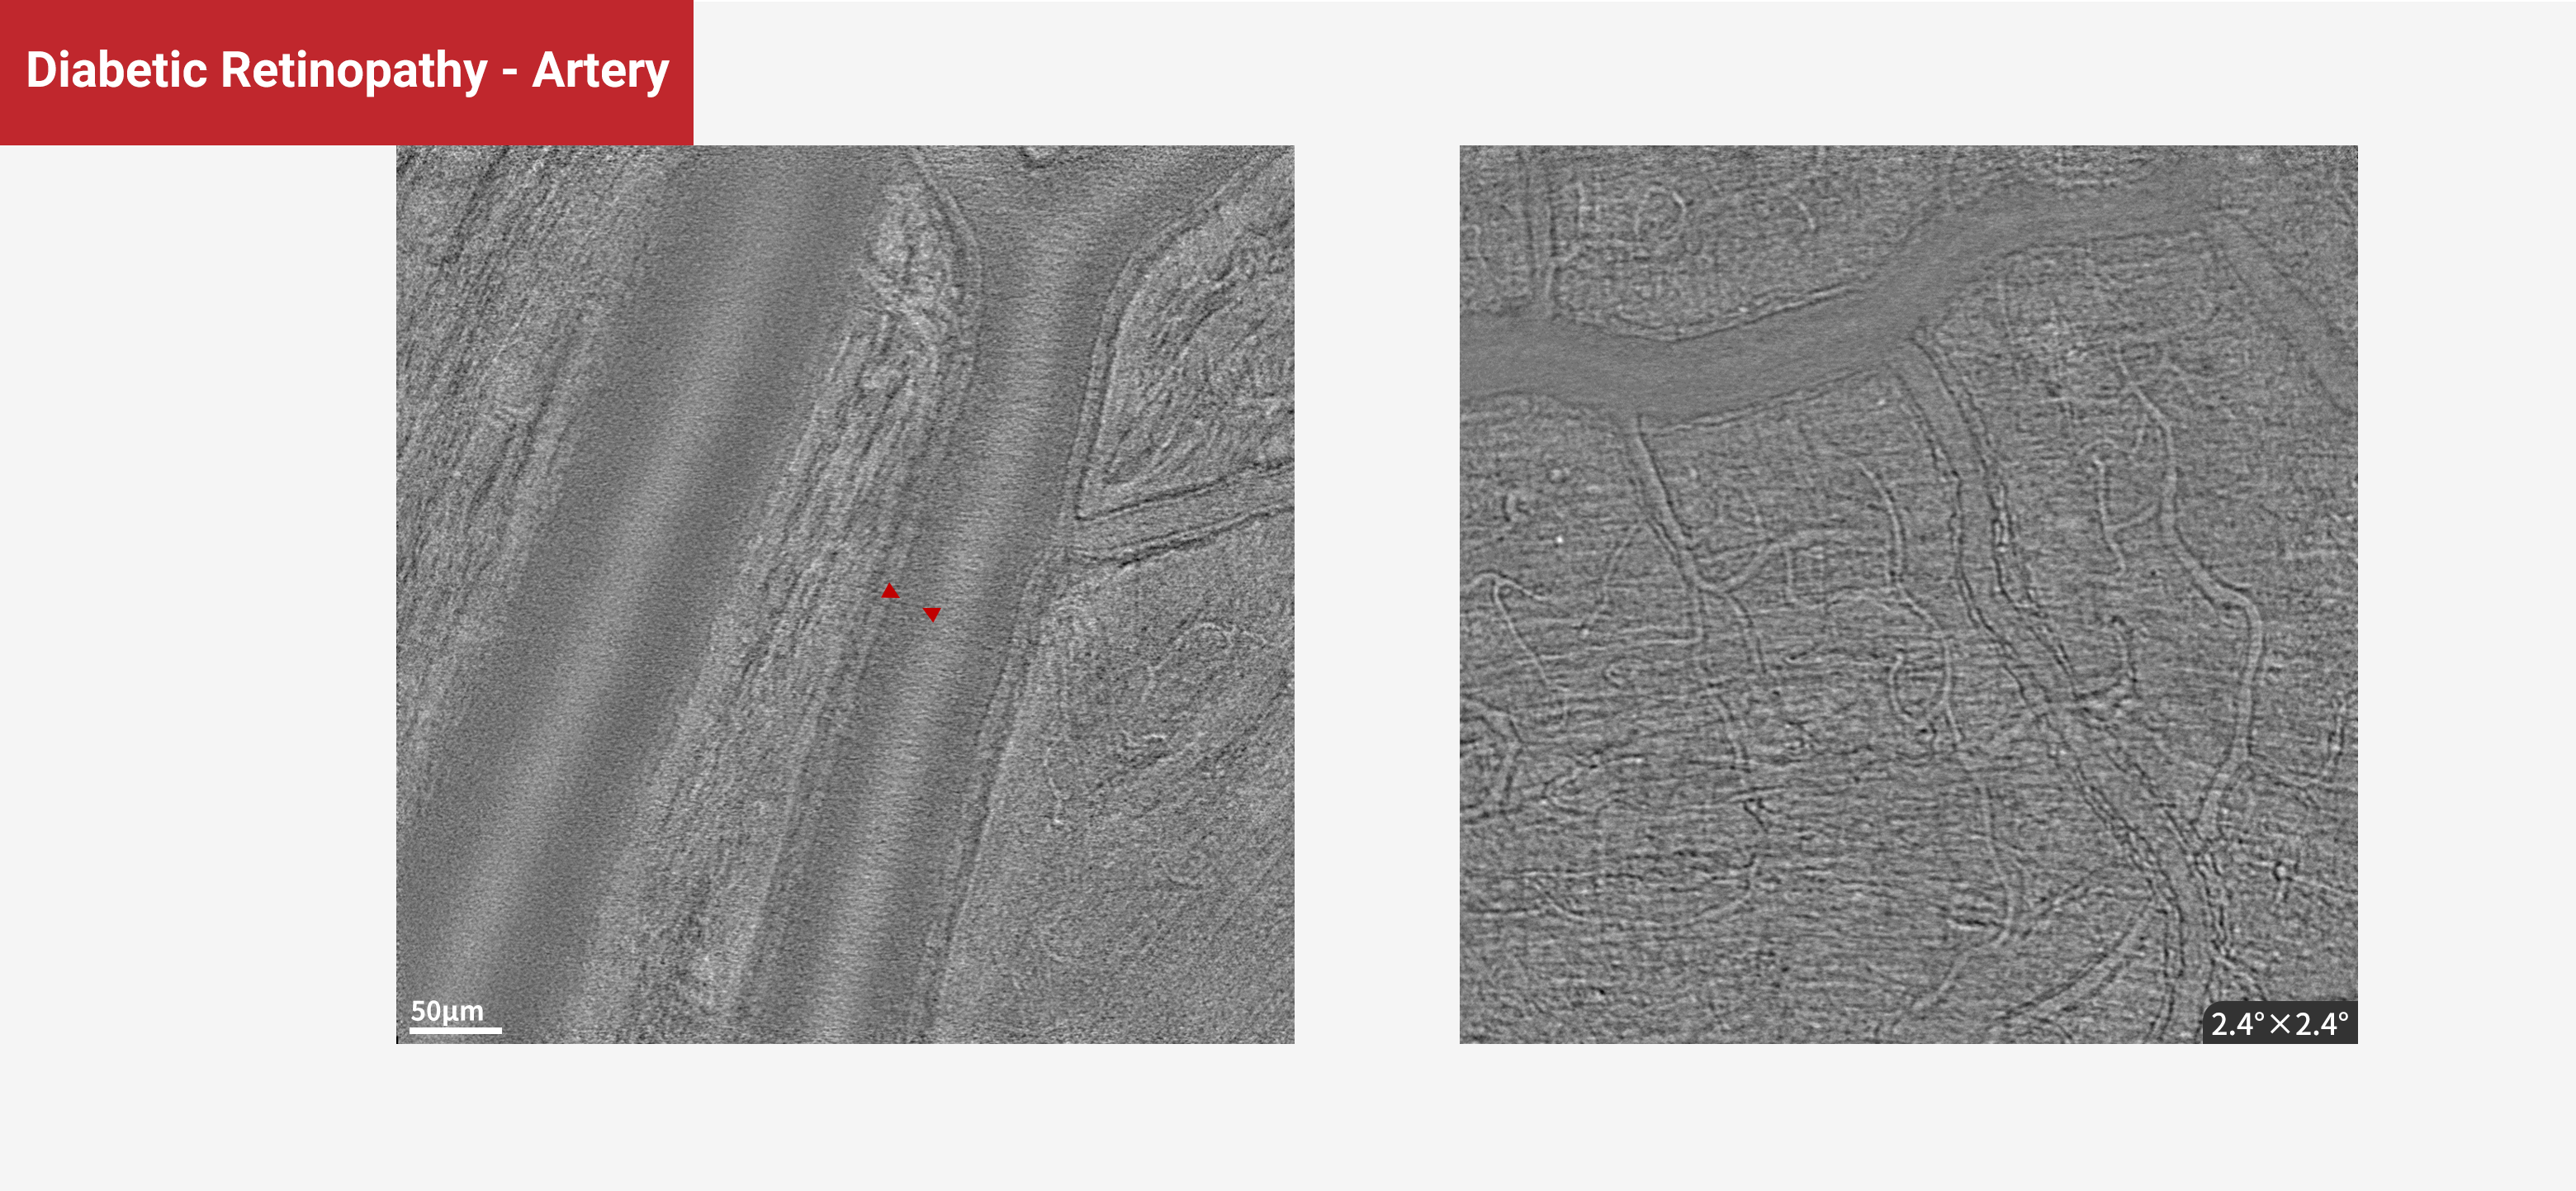

Diabetic Retinopathy - Artery